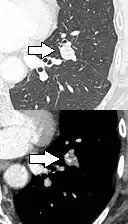

- Location: Upper lobe location is a risk factor for cancer, while a location close to a fissure or the pleura indicates a benign lymph node,[8] especially if having a triangular shape.[9]

subpleural nodule.[9]

Round well-delineated solid lung nodule with smooth border.[9]

Lobulated nodule.[9]

Spiculated lung nodule.[9]

A "notch sign".[9]

A triangular perifissural node can be diagnosed as a benign lymph node.[9]